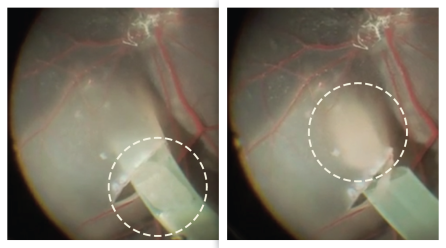

In this clinical trial, nurses at NYSCF will collect blood from each patient. NYSCF scientists will then turn their blood cells into stem cells, and then into retinal cells. These retinal cells will be placed onto a patch which will be transplanted into the eye. Because this patch is biodegradable, the surgery will leave no trace other than 100,000 new retinal cells, which will integrate into the region of the eye damaged in AMD.

The surgical team is led by Columbia University’s renowned ophthalmologist Dr. Stanley Chang, working closely with Dr. Stephen Tsang and Dr. Tongalp Tezel. This clinical trial is among the first in the world to restore vision using a patient’s own cells. This personalized approach will remove the risk of transplant rejection, precluding the need for immune suppression.